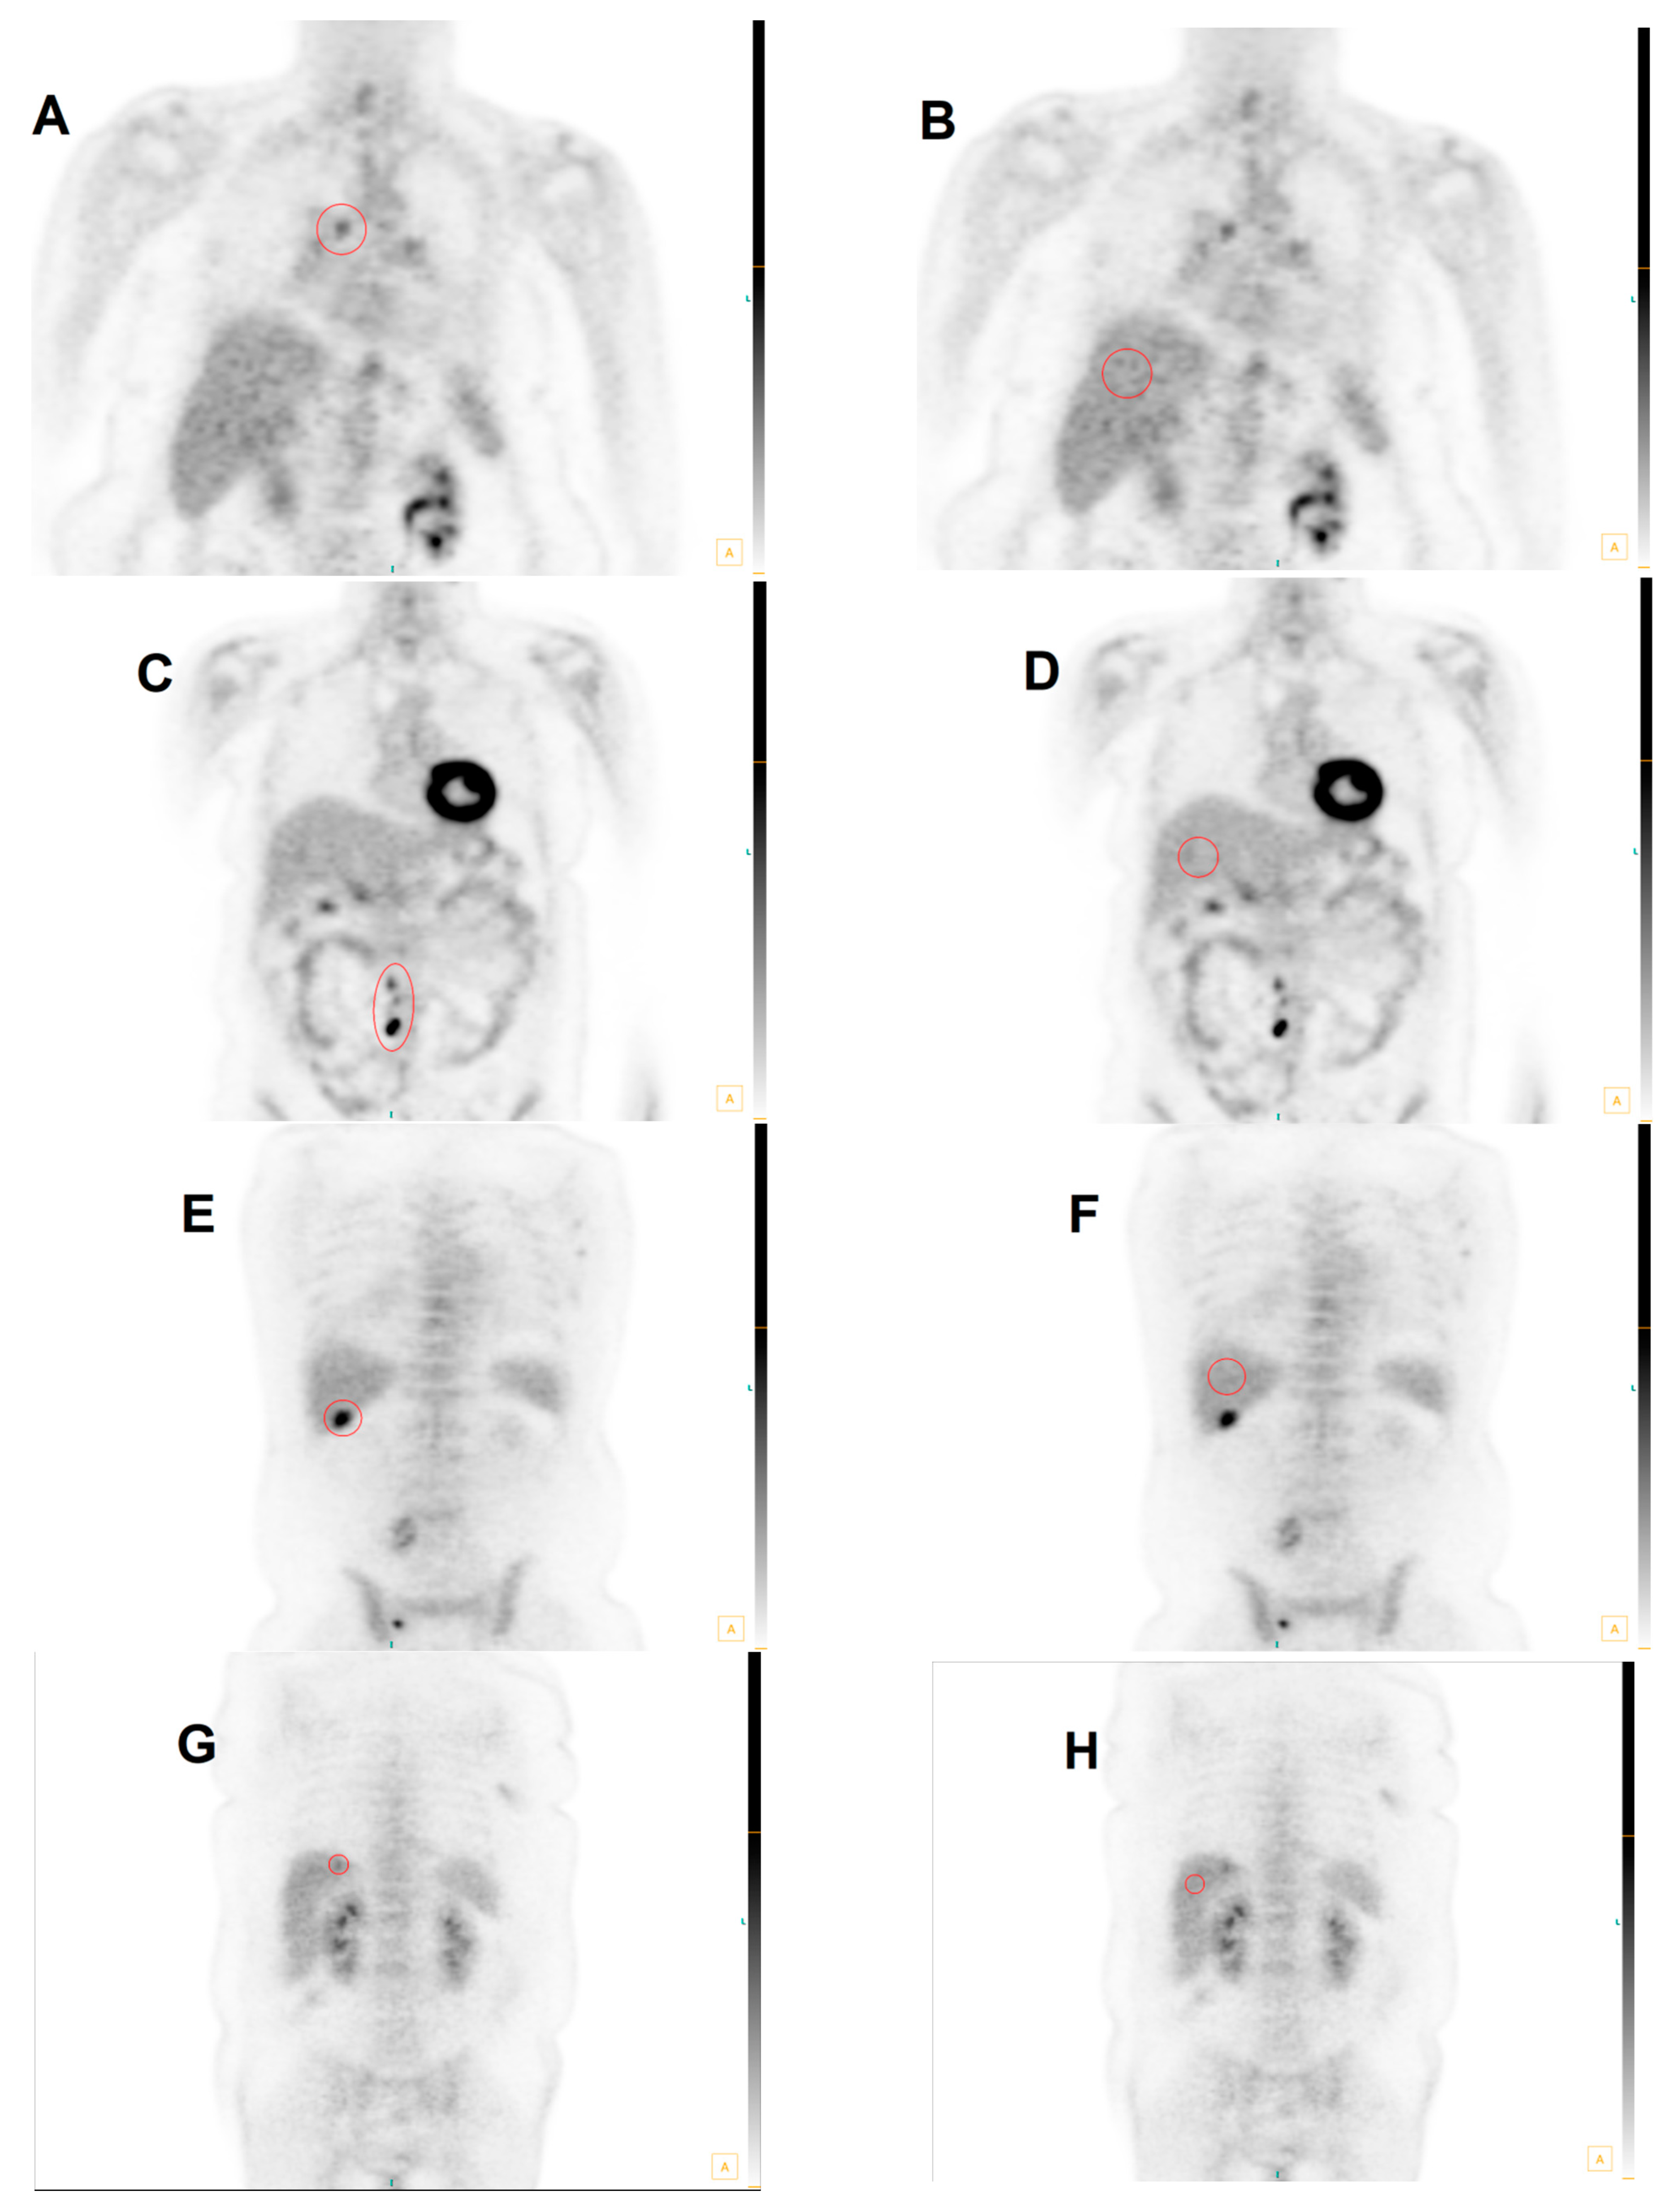

3.2. Group 1: MHLN Lung Cancer Cohort

3.3. Group 2: ETLN Cohort

3.4. Group 3: Hepatic Parenchymal Colorectal Carcinoma Cohort

3.5. Total Cohort